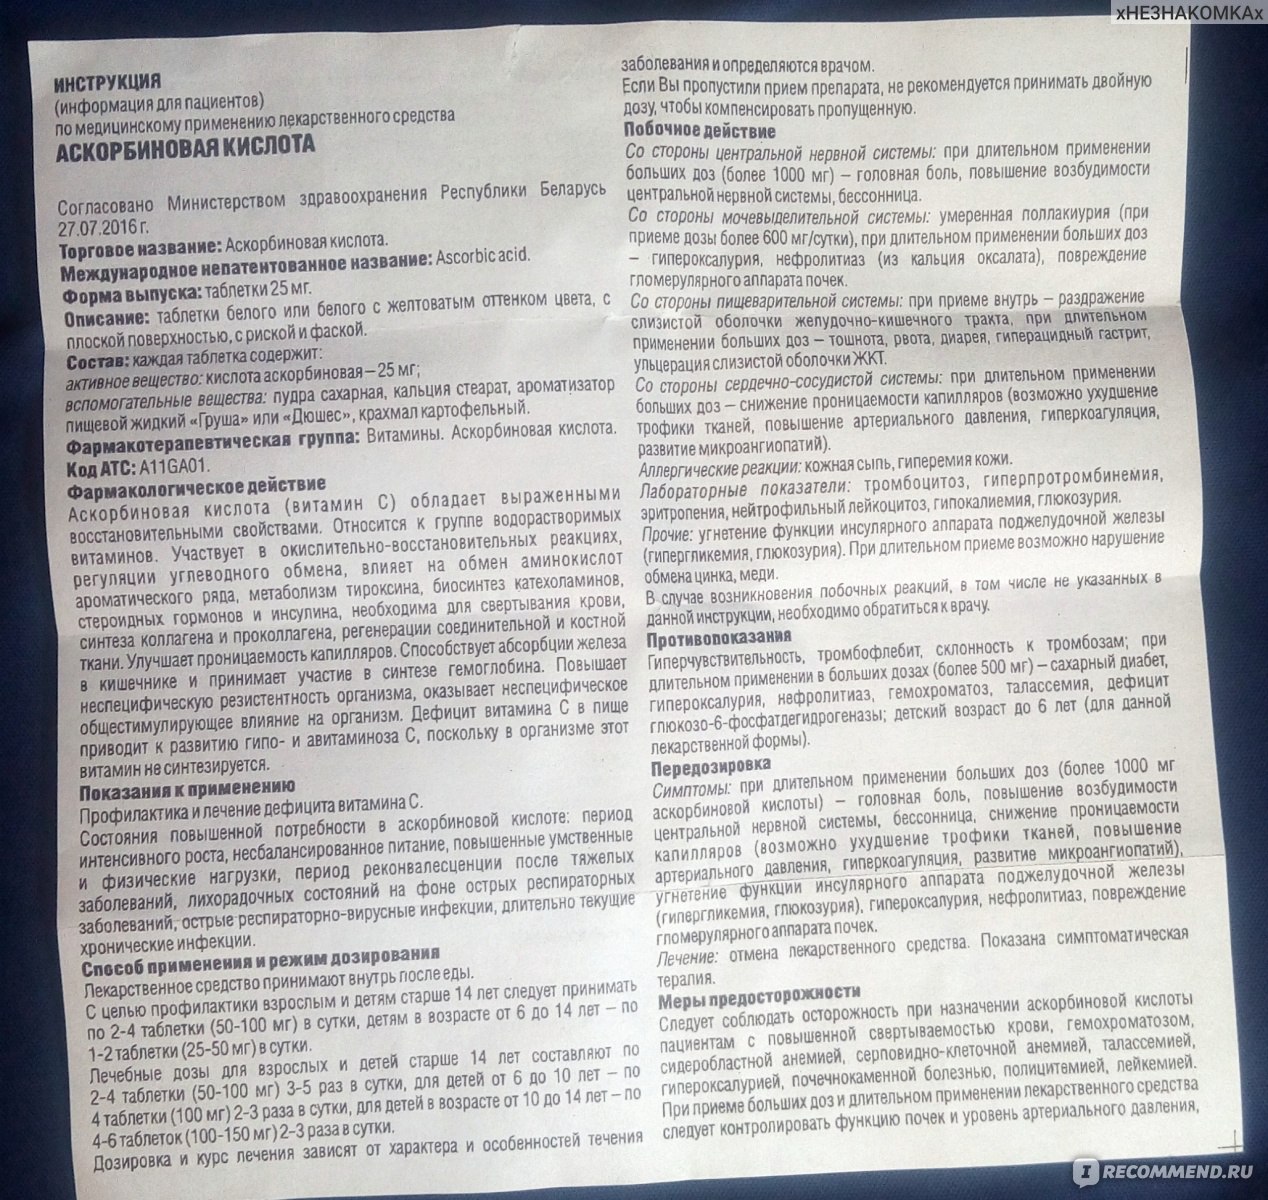

Здоровье женщин и его взаимосвязь с миром животных